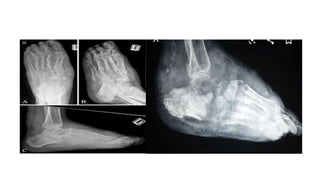

RADIOLOGIC FEATURE

• Early stage—soft tissue granuloma appear as soft tissue shadow with

calcification and obliteration of facial plane.

• Bone scalloping from external pressure seen.

• Periosteal reaction seen.

• Late stage-punched out cavities after multiple may appear that have

well defined margin.

• Actinomycetic-cavity small numerous with no defined margin (moth

eaten appearance).

• Usg-differentiate the mycetoma from osteomyelitis

tumour.

• Eumycetoma-sharp hyperechoic focus.

• Actinomycetoma-fine hyperechoic focus.

• MRI-dot in circle sign.

RADIOLOGIC FEATURE • Earlystage—soft tissue granuloma appear as soft tissue shadow with calcification and obliteration of facial plane. • Bone scalloping from external pressure seen. • Periosteal reaction seen. • Late stage-punched out cavities after multiple may appear that have well defined margin. • Actinomycetic-cavity small numerous with no defined margin (moth eaten appearance).

• 15.

• Usg-differentiate themycetoma from osteomyelitis tumour. • Eumycetoma-sharp hyperechoic focus. • Actinomycetoma-fine hyperechoic focus. • MRI-dot in circle sign.